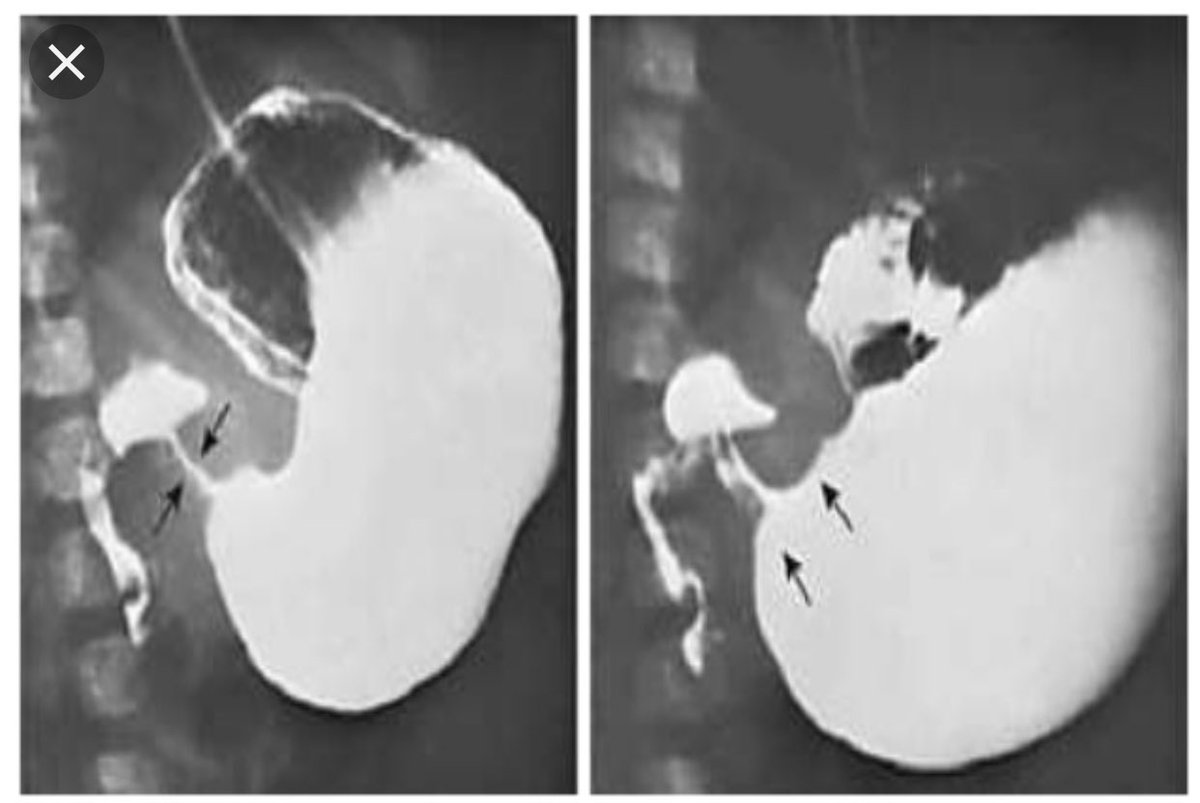

DBMCI Egurukul - ❓Upper GI series demonstrating a narrow and elongated pylorus with a narrow lumen (“string sign”), appearing as puckering of the mucosa (“double track sign”) is a feature of❓ A. The Gastrointestinal String Sign | Radiology Hypertrophic pyloric stenosis- “string sign” | Pediatric surgery, Pediatrics, Radiology Peds in a Pod on X: "If you've listened to Poopcast 3.0, check out this image of the “String sign” for pyloric stenosis. This is a the finding from an UGI, which Hypertrophic pyloric stenosis. ( ) A diagrammatic representation of the... | Download Scientific Diagram Pyloric Stenosis String Sign